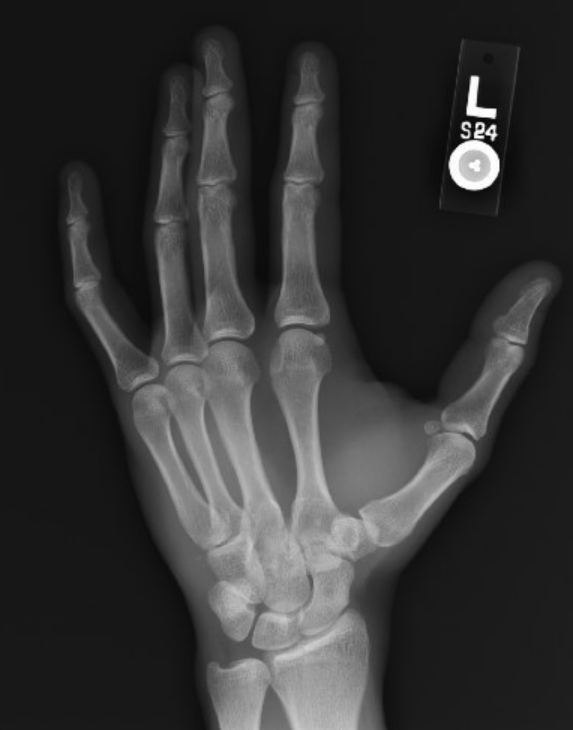

Post-reduction images: